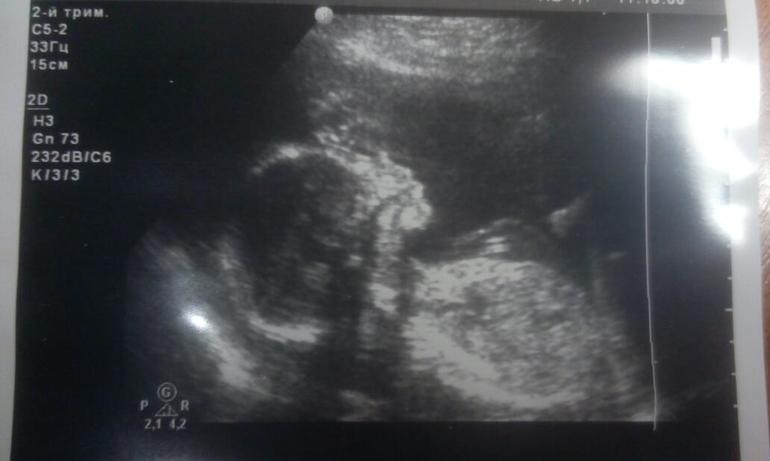

ЭкваторДавно не писала и получилось все в кучу)))Перешагнули мы экватор,прошли второе узи.С малышом все хорошо,иии у на мальчик))).но не все совсем гладко.Подробности ниже.И фотопуз,не спешим мы расти)))У кого какой животик в 21 неделю?)

Во превых на узи нам поставили низкую плацентацию,ну время есть надеюсь поднимется еще.Второе- в околоплодных водах увидели взвеси( немного,но есть)это следствие воспаления либо инфекции.Была у врача,сдала анализы,сейчас жду ответы.Надеюсь ничего серьезного,я оптимист))) Дали нам фото мальчика нашего) иии началась эпопея с именем...папе нашему свекр навязывает имя Миша(отца свекра так звали),при том,что отношение к моим детям он имеет только кровное,все,никакого хоть малейшего внимания и нтереса с его стороны нет,видит наших детей раз в год,и то когда муж их берет с собой.В общем я категорически против,раз уже попугались из- за этого,принесла книгу с именами,думаем,пока на месте,но опять же время есть))))) Покупки еще не начинали,только вяжу понемногу.Вкусовых пристрастий особых нет,люблю фрукты- ягоды,овощи и не могу без печеного) Ну и вот наши фотографии